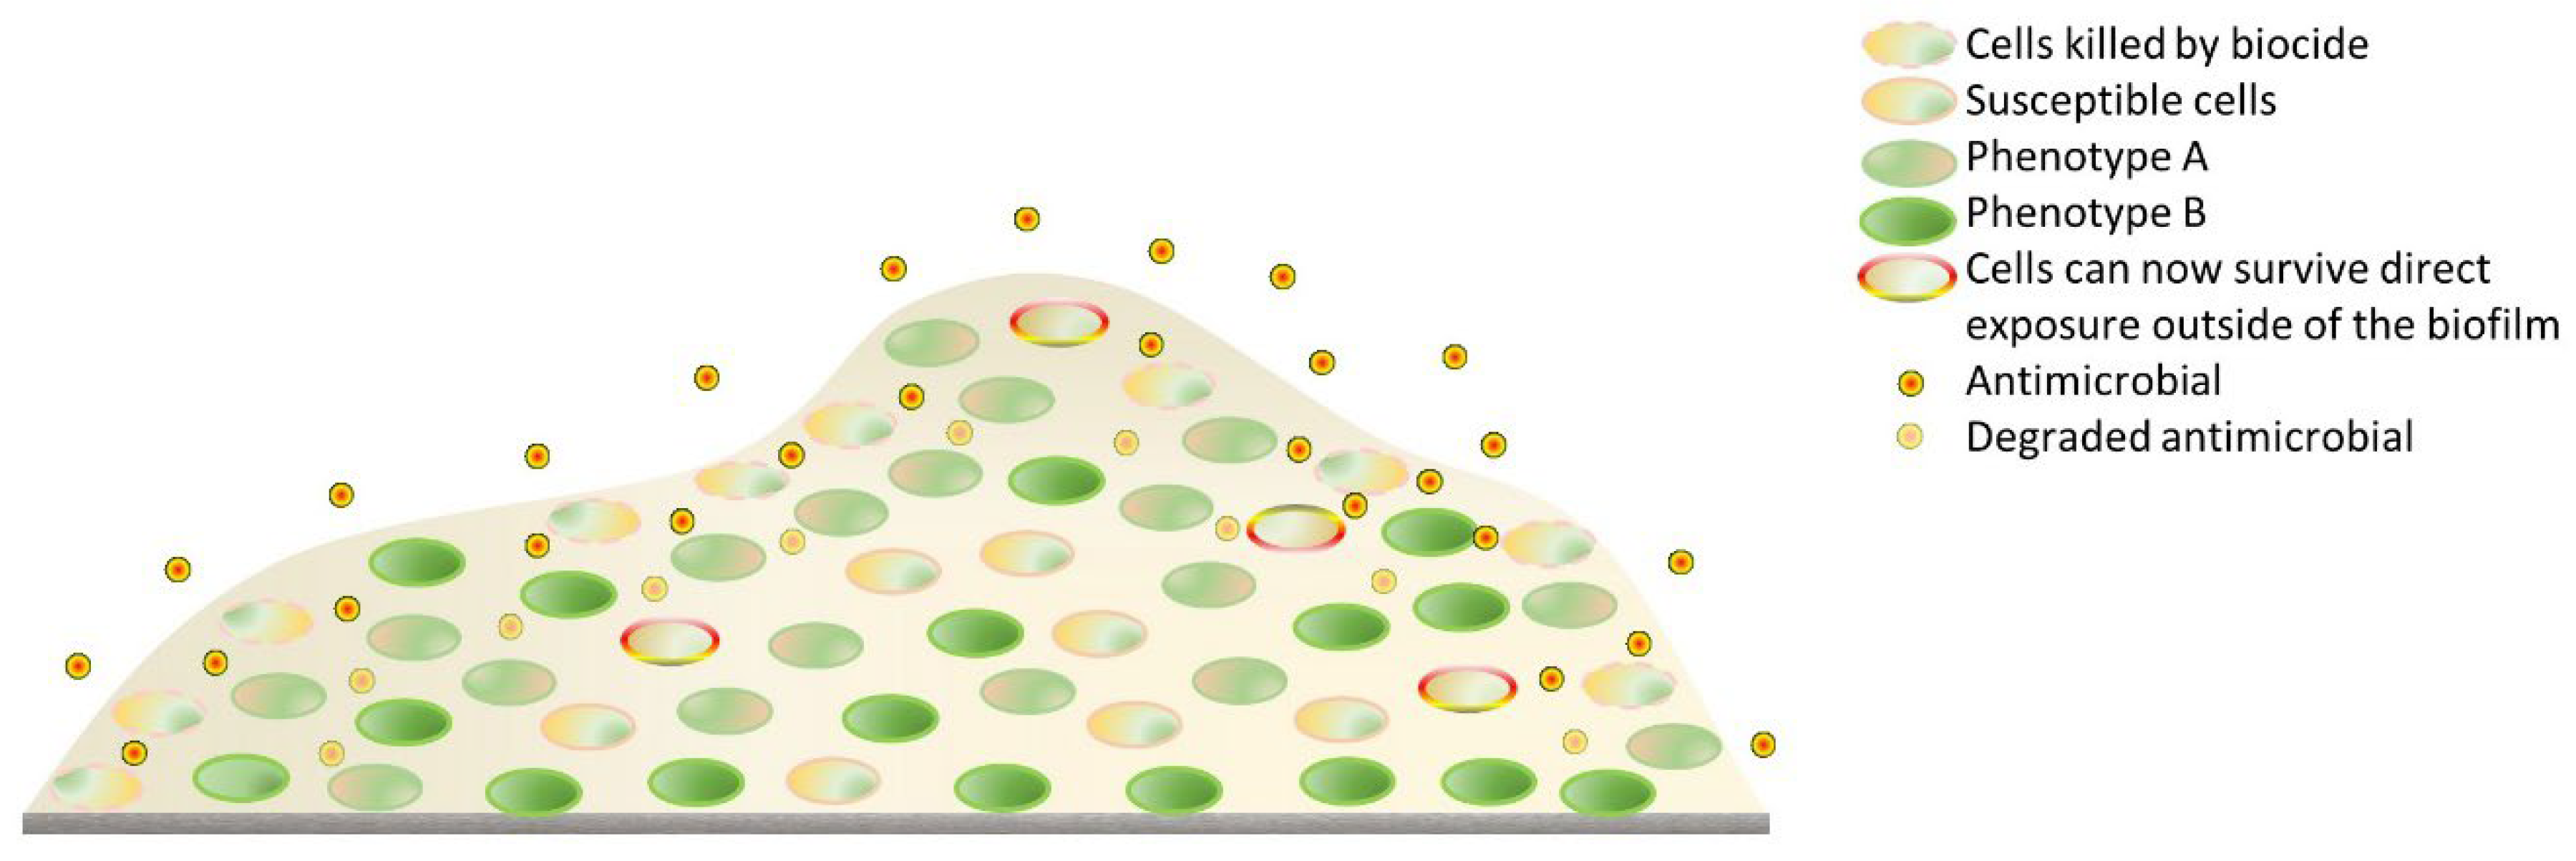

- Flemming, H.-C.; Wingender, J.; Szewzyk, U.; Steinberg, P.; Rice, S.A.; Kjelleberg, S. Biofilms: An Emergent Form of Bacterial Life. Nat. Rev. Microbiol. 2016, 14, 563–575. [Google Scholar] [CrossRef] [PubMed]

- Otto, M. Staphylococcal Infections: Mechanisms of Biofilm Maturation and Detachment as Critical Determinants of Pathogenicity. Annu. Rev. Med. 2013, 64, 175–188. [Google Scholar] [CrossRef] [PubMed]

- Koo, H.; Allan, R.N.; Howlin, R.P.; Stoodley, P.; Hall-Stoodley, L. Targeting microbial biofilms: Current and prospective therapeutic strategies. Nat. Rev. Microbiol. 2017, 15, 740–755. [Google Scholar] [CrossRef] [PubMed]